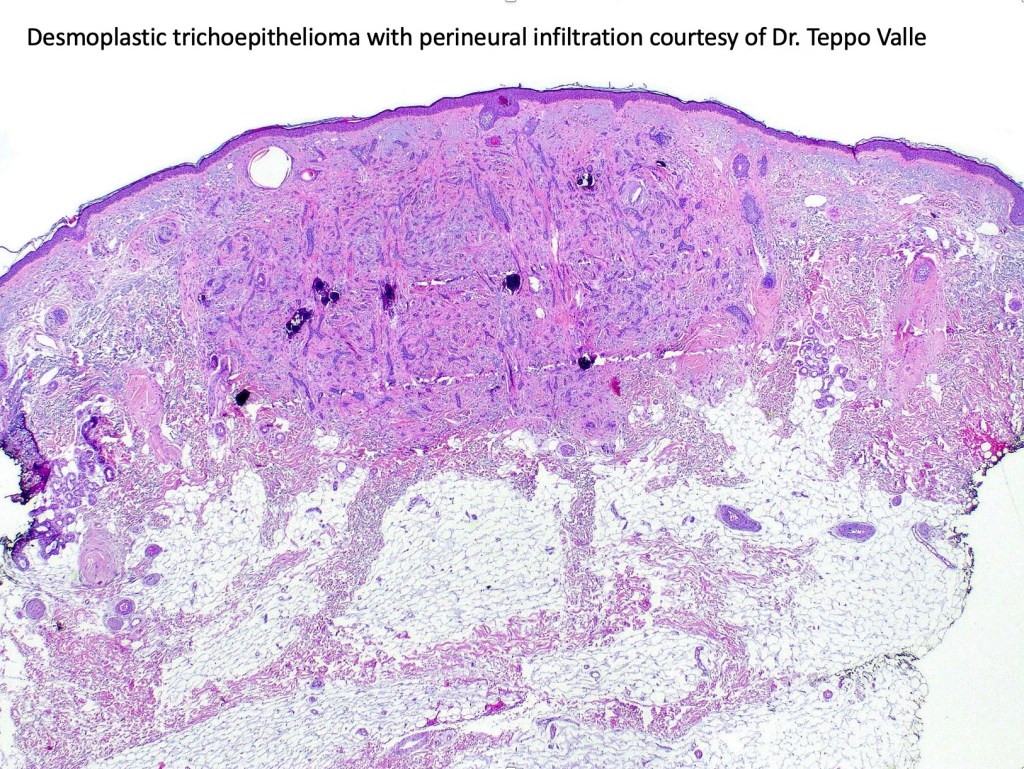

Histological features

•Consists of narrow epithelial strands & keratocysts embedded in a dense stroma

•Generally involves superficial & mid dermis but does not extend into the subcutaneous fat

•Perineural infiltration is documented but is exceptional & makes differentiation from MAC difficult